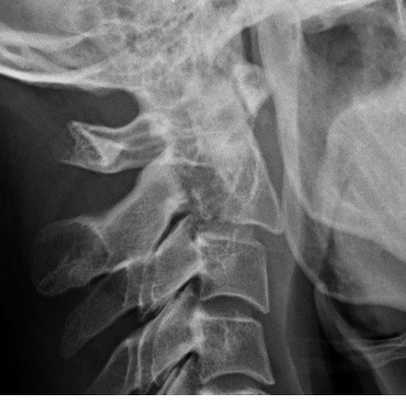

(Слева) Рентгенограмма в боковой проекции: снижение высоты переднего отдела межтелового пространства С6-С7, расширение межостистого промежутка и дистракционное повреждение дугоотростчатых суставов (смещение суставных поверхностей относительно друг друга > 50%).

(Справа) На аксиальном GRE МР-И у пациента с флексионной травмой шейного отдела позвоночника видно массивное паренхиматозное кровоизлияние в центральной части спинного мозга, характеризующееся в этом режиме низкой интенсивностью сигнала. Такая картина является плохим прогностическим признаком возможности полноценного функционального восстановления. (Слева) Рентгенограмма в боковой проекции: расширение промежутка между остистыми отростками С6 и С7. Нижний суставной отросток С6 находится впереди верхнего суставного отростка С7.